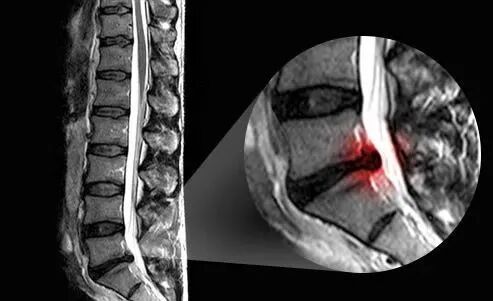

当我们的腰椎间盘受到过度的应力、先天椎体周边韧带不够强健、老化、反复的不正确使用或者是外伤以及其他一些原因会导致我们的腰椎间盘发生退变,产生一些无菌性的炎症,导致患者出现弯腰、蹲起等活动时明显的腰部疼痛。大家看下图就可以明白,腰椎间盘退变和正常腰椎间盘的区别。

同时导致保护髓核的纤维环结构发生退变、老化以及碎裂,髓核就会像椎间盘的周围突出,当刺激到位于椎体后方椎管内的神经根的时候,就会导致患者出现坐骨神经痛。

当突出的程度明显加大,对于椎管内结构造成了特别大的挤压,尤其是会压迫到位于椎管内马尾神经的时候,会出现马尾神经综合症。